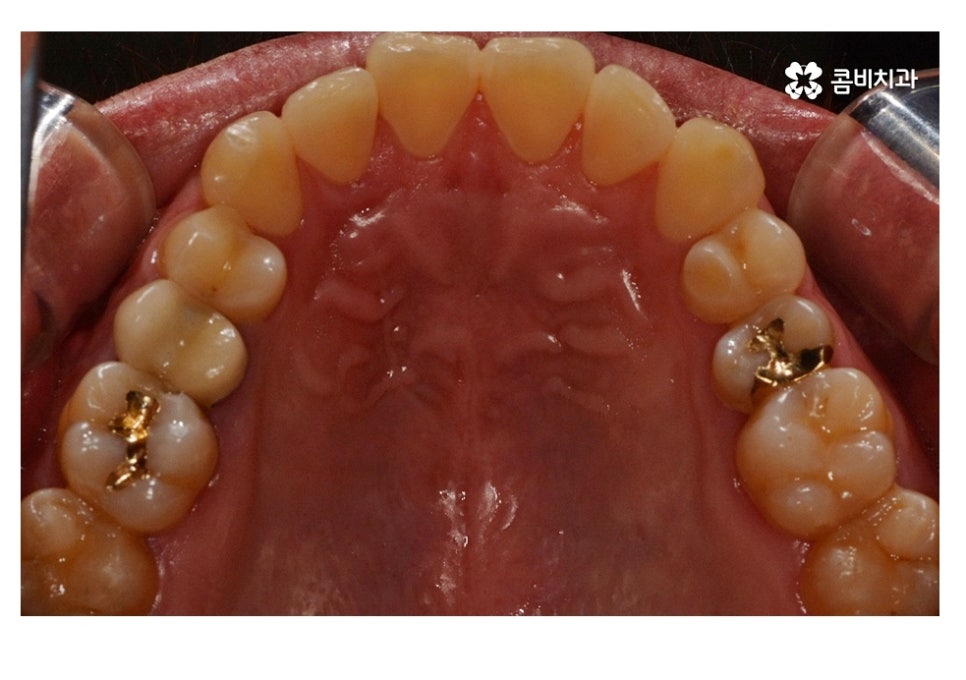

위 사례 이미지에서 보시는 것과 같이 불규칙한 치열 외에도

치아 사이가 벌어져 있으면 심미성 뿐 아니라

음식물이 치아 사이에 끼기 쉽기 때문에 충치, 잇몸질환이

발생하기 쉬울 수 있어요.